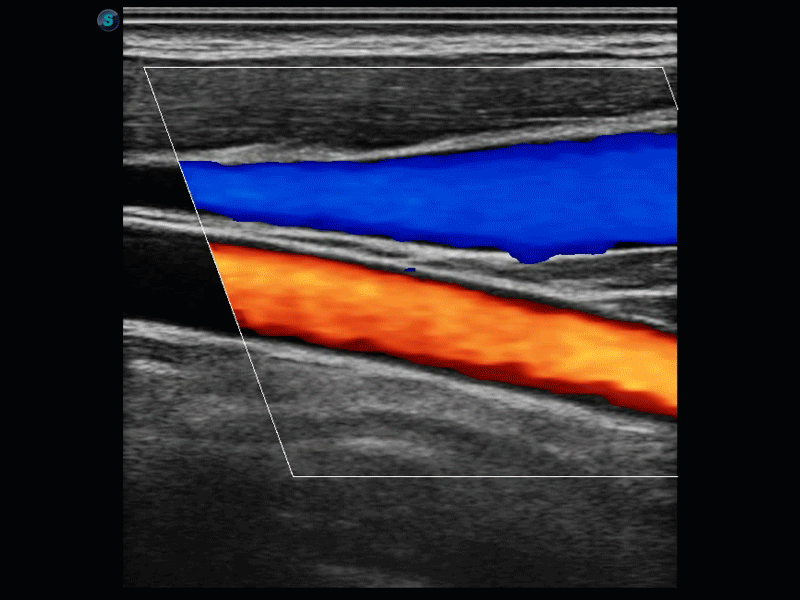

复合材料线阵探头

凭借狗万官方网站先进的成像技术和优异的探头技术提供的清晰的图像表现,您可以更自信地做出临床决策。